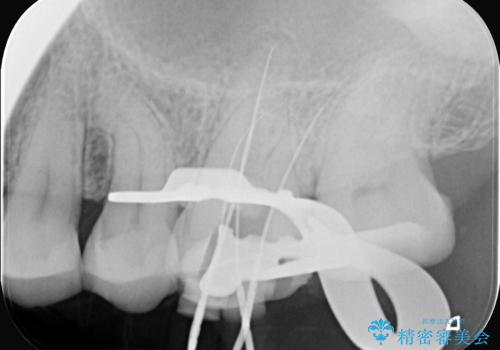

治療はまず、感染源を徹底的に除去する根管治療から開始しました。治療の精度を高めるため、ラバーダムや顕微鏡などを使用し、根管内を丁寧に清掃・消毒。これにより、痛みの原因を根本から取り除きました。